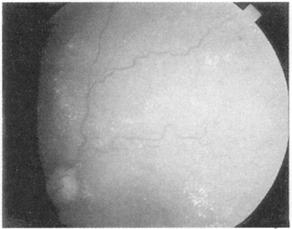

在熟悉之前你需要看一些视网膜图,花时间去注意黄斑,为一淡红色斑点。按顺序描述你的所见为佳,寻找背景,不是乳头或黄斑,而是出血和渗出,检查视网膜血管,注意粗细和规则——小动脉的直径是静脉的2/3,分布规则。正常的视乳头和糖尿病、高血压、乳头水肿和视神经萎缩见图(图151~155)。

图152 糖尿病眼底的改变,可见斑点状出血和渗出